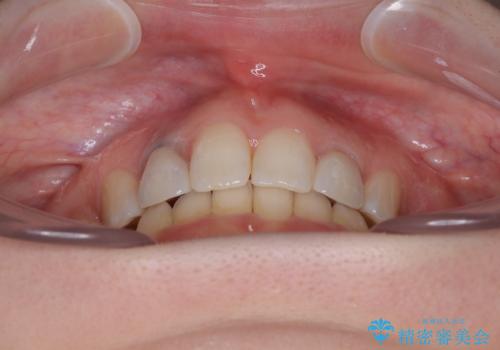

飛び出した上顎前歯とむし歯の多い歯列 目立たないハーフリンガル矯正とむし歯治療

抜歯したスペースがなかなか閉じず、治療に時間はかかりましたが、術前術後のむし歯治療と合わせて3年10ヶ月で治療を終えることができました。

途中結婚により遠方に引っ越しをされたため、むし歯治療は取り急ぎ目立つところをセラミッククラウンとしましたが、今後落ち着いてきたら他の部分も行っていく予定です。